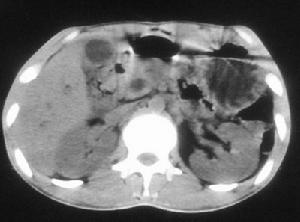

B型超声肝胆扫描 慢性胆囊炎是最常见的一种胆囊疾病,病人一般同时有胆结石,但无结石的慢性胆囊炎病人在我国也不少见。慢性胆囊炎有时可为急性胆囊炎的后遗症,但大多数病人过去并没有患过急性胆囊炎,由于胆囊长期发炎,胆囊壁会发生纤维增厚,疤痕收缩,造成胆囊萎缩,囊腔可完全闭合,导致胆囊功能减退,甚至完全丧失功能。 医学百科网 | YxBaike.Com

胆囊造影和B型超声肝胆扫描是诊断慢性胆囊炎很有价值的检查方法。胆囊造影可以发现胆结石、胆囊缩小变形,以及浓缩和收缩不良等情况,有时胆囊不显影。B超检查除了可探查出胆结石和胆囊外型改变以外,还能看到胆囊壁有变毛糙、增厚等征象。有上述症状的病人,应及时就医,通过以上检查,一般可以明确慢性胆囊炎的诊断。